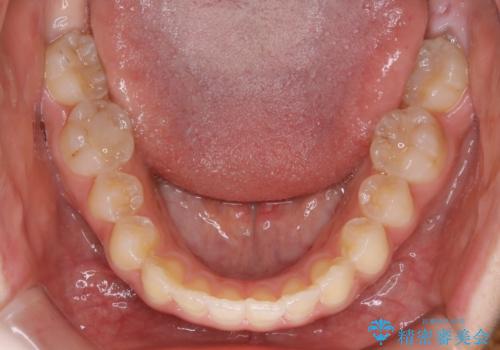

短期間ですきっ歯を改善:インビザラインLite

- 上の歯がすきっ歯なのと、歯が出ている気がするとご相談にいらした方です。

奥歯の噛み合わせに大きな問題がなく、患者様のご希望もあったため、前歯部メインで治療するインビザラインLiteで治療を行いました。

日常的に舌を突出する癖があったため、後戻り防止のために舌および口唇の筋機能訓練も合わせて行いました。

横顔のシルエットが改善し、口元もスッキリとなりました。